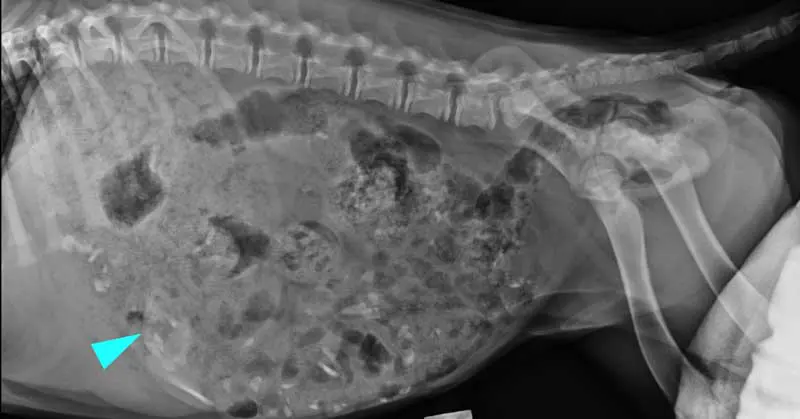

An ultrasound revealed his stomach was markedly distended and filled with a large amount of kibble – believed to have been scavenged earlier in the day from a food cupboard – before a lateral abdominal radiograph showed the object was still inside him.

The foreign body – measuring 6.5 cm by 3.5 cm – was removed with forceps via endoscopic retrieval under general anaesthesia before it could cause gastrointestinal trauma or obstruction.

The sizeable spatula head measured 6.5cm by 3.5cm.